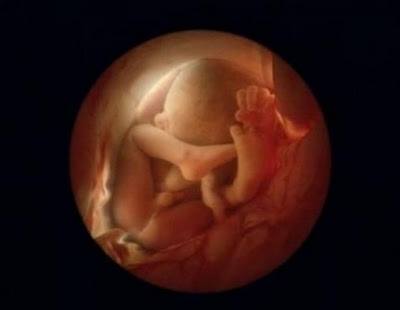

Պտուղն արդեն 16 շաբաթական է:

16 շաբաթական պտուղն սկսում է օգտագործել ձեռքերը, որպեսզի ուսումնասիրի սեփական մարմինը:

6 ամսական պտուղ

4 շաբաթ անց փոքրիկը լույս աշխարհ կգա: